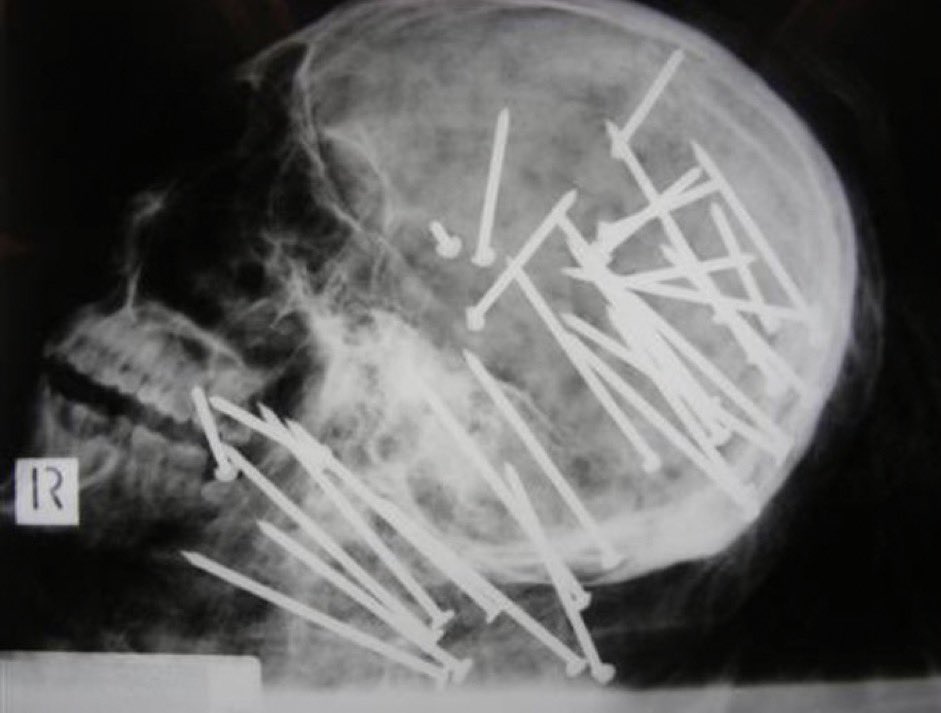

3. تكشف هذه الأشعة السينية المرعبة عن النهاية المأساوية لتشن ليو، وهو رجل يبلغ من العمر 27 عامًا تم اكتشافه في المستنقعات بالقرب من سيدني، أستراليا. لقد قُتل بوحشية، حيث تم طعن جسده بـ 34 مسمارًا.